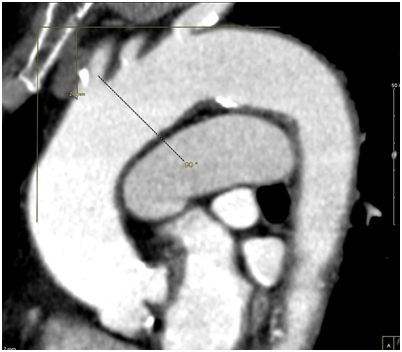

Figure 2 Coronal section showing origin of innominate artery > 2 L CCA diameter from top of arch in type III aortic arch in one of our TAVR patients.

Baseline characteristics and demographics are shown in Table 1. Among our 61 study patients, there were 36 Type I AAs, 9 Type II AAs and 16 Type III AAs. The mean age of participants was 51.8 + 19.6, 72.2 + 12.3 and 80.6 + 12.7 years for Type I, II and III arches respectively. Cardiac mass indices were significantly different in the 3 AA types with increasing mass in type II and III compared to type I (Table 2–4 and Figure 1). Univariate analysis revealed increased age (p< 0.001), LV weight index (p=0.002) and LVPWd (p=0.01) had significant correlation with Type II and III AAs, however, after multivariate analysis only increased age and LV weight (our surrogate for the cardiac weight) remained independent predictors of AA type. Furthermore, 10 of 11 (91%) elderly patients within our cohort who had severe aortic stenosis (patients one would expect to have the greatest LV weight for the longest time) had a Type III arch (Figure 2).